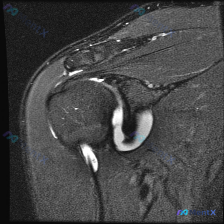

整理了一份肩部MRI读片病例,问题是发现软组织积液后该怎么分析,给大家分享一下完整思路。 病例影像基础信息 这是一份肩部MRI T2序列冠状位图像,我们先把核心观察点列出来: 1. 冈上肌腱:附着于肱骨大结节区域,局部信号显著异常增高,和液体信号强度接近,肌腱连续性在附着点处中断,形态不规则 2....